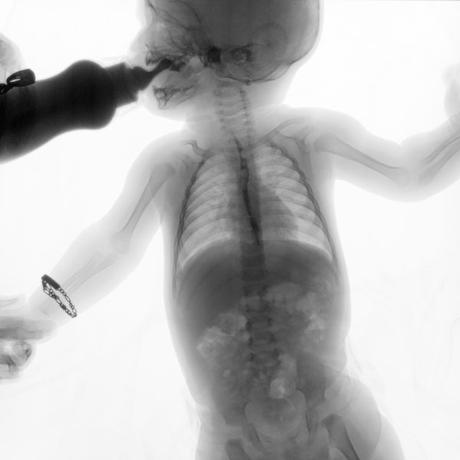

ESTUDIO SOLICITADO: SERIE ESOFAGOGASTRODUODENAL.

Se realiza Esofagograma con material de contraste baritado, por vía oral y por medio de control fluoroscópico se toman distintas proyecciones observando lo siguiente.

Se observa mecánica de la deglución con adecuado paso de medio de contraste de faringe a esófago sin presencia de defectos de llenado depósitos anómalos o fuga del mismo.

ESÓFAGO se observa de situación, calibre y trayecto normal. Contornos regulares y bien definidos. No se observan depósitos anómalos, defectos de llenado o fuga del medio de contraste.

UNION ESOFAGOGASTRICA se observa con calibre y situación normal. Sin observar reflujo a las maniobras de valsalva

ESTOMAGO se observa en su situación habitual, distendido, sin defectos de llenado.

- Actualmente no se demuestra Reflujo gastro-esofágico.

- Estudio de apariencia normal.